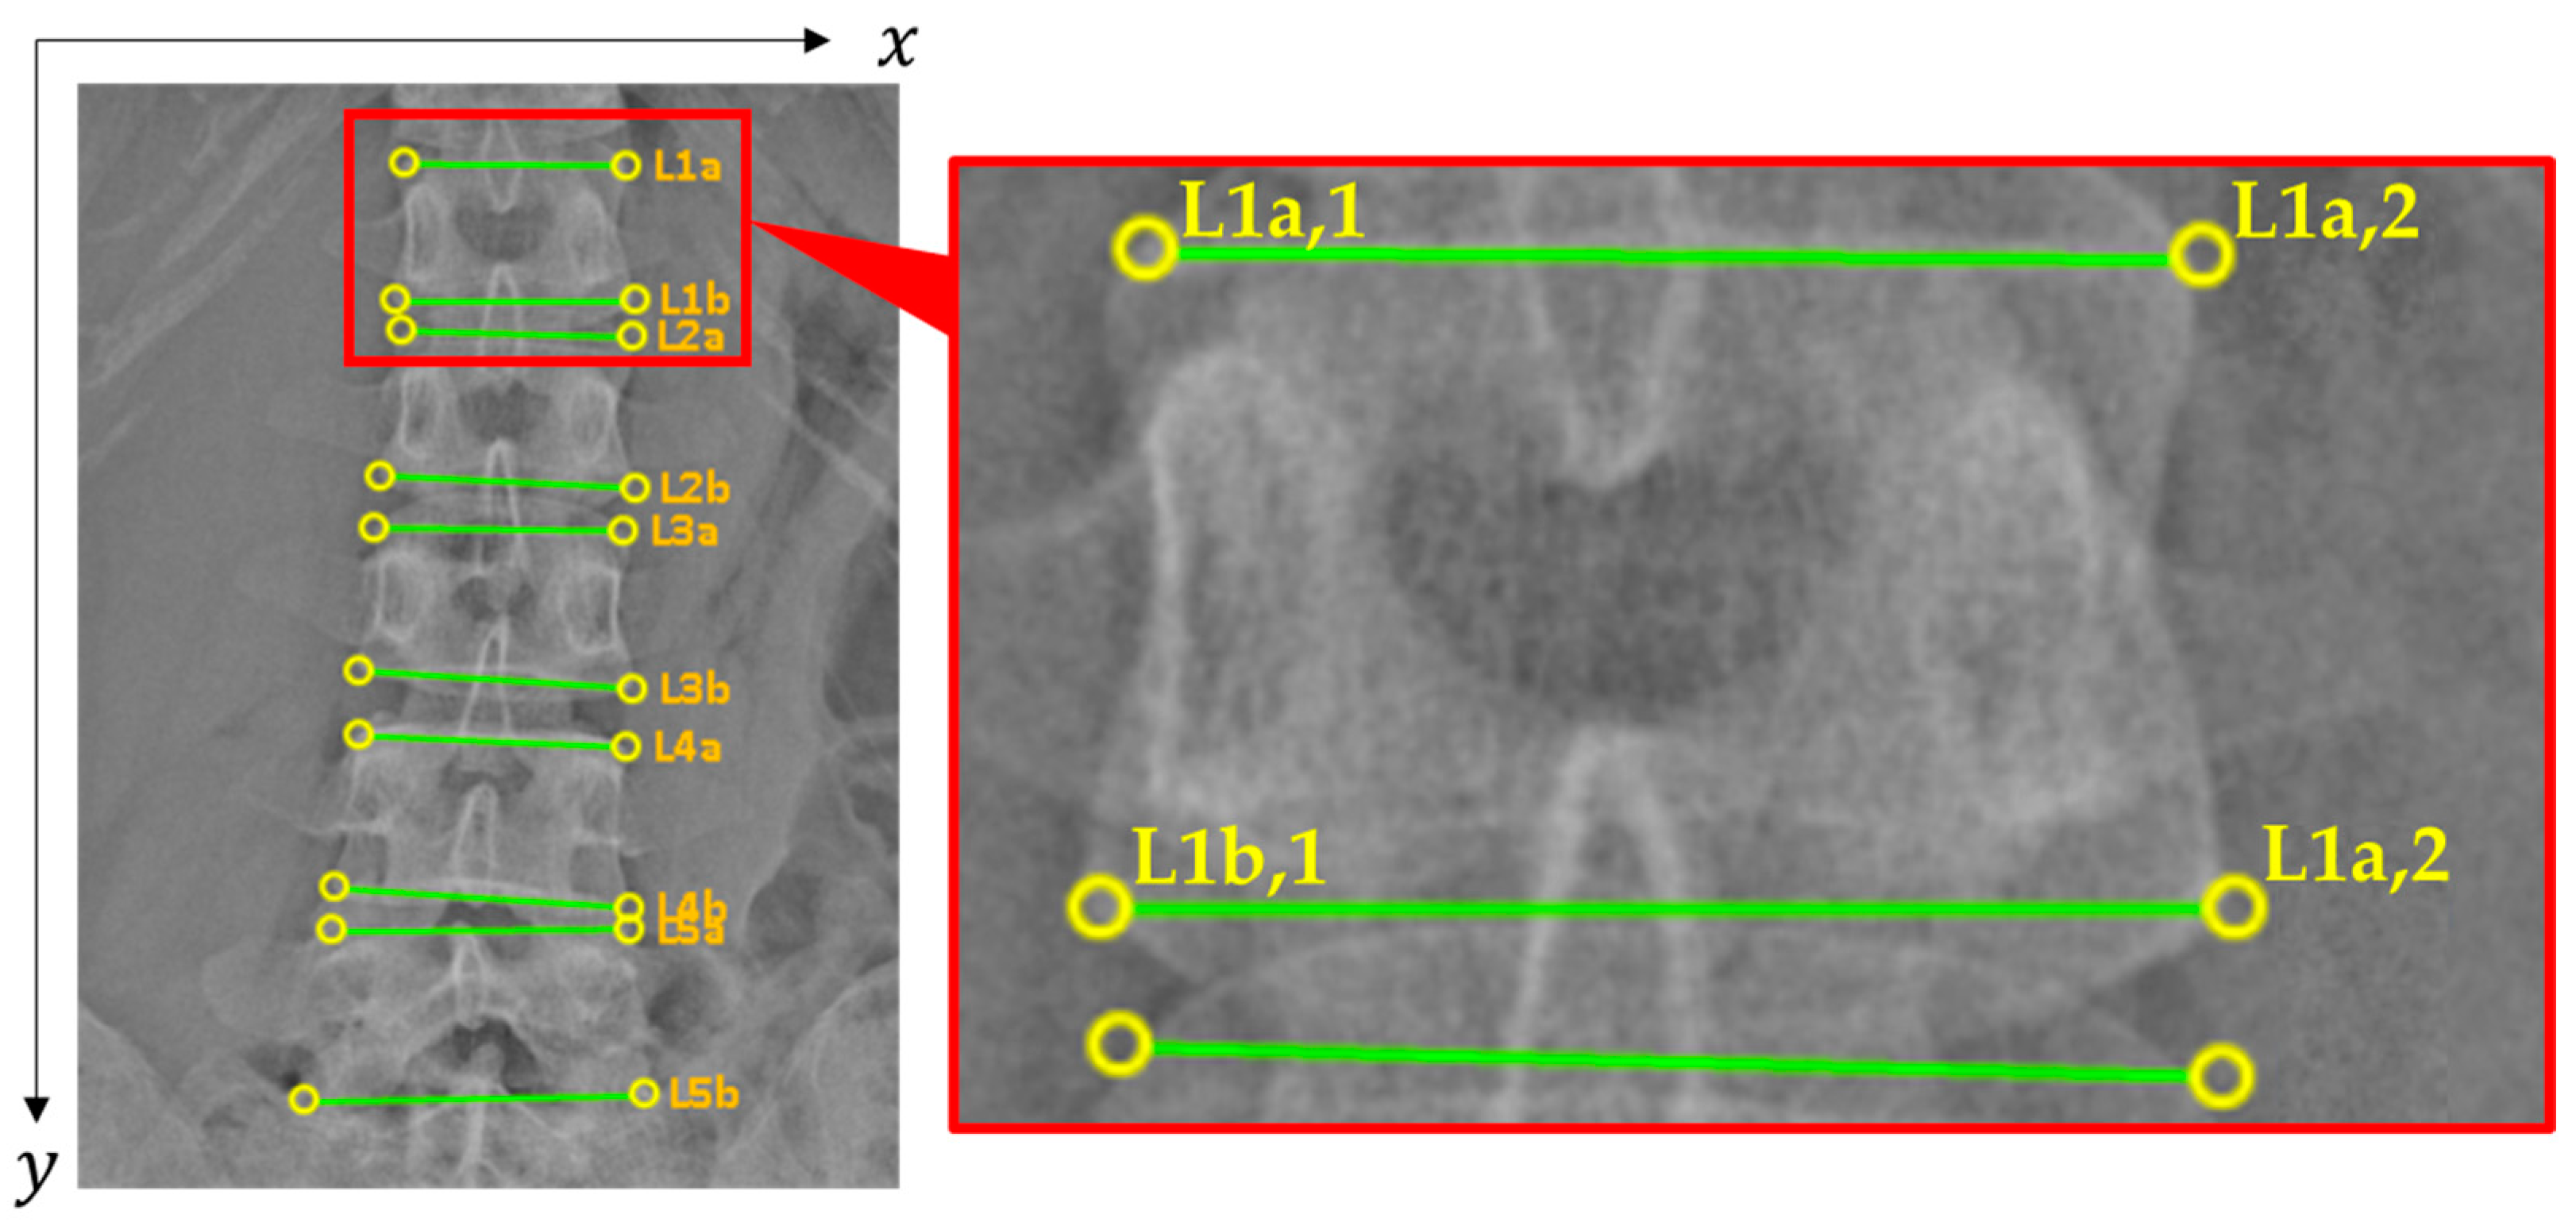

2.2.1. Vertebral Positions

| Line | x1 | y1 | x2 | y2 | Class |

|---|---|---|---|---|---|

| L1a | 876 | 167 | 1111 | 169 | ✕ 1 |

| L1b | 866 | 314 | 1120 | 314 | 0 |

| L2a | 871 | 344 | 1117 | 351 | ✕ 1 |

| L2b | 848 | 498 | 1120 | 511 | 0 |

| L3a | 842 | 553 | 1109 | 557 | ✕ 1 |

| L3b | 825 | 706 | 1118 | 725 | 0 |

| L4a | 826 | 775 | 1112 | 787 | ✕ 1 |

| L4b | 801 | 937 | 1114 | 958 | 0 |

| L5a | 798 | 983 | 1115 | 980 | ✕ 1 |

| L5b | 767 | 1164 | 1129 | 1158 | 0 |